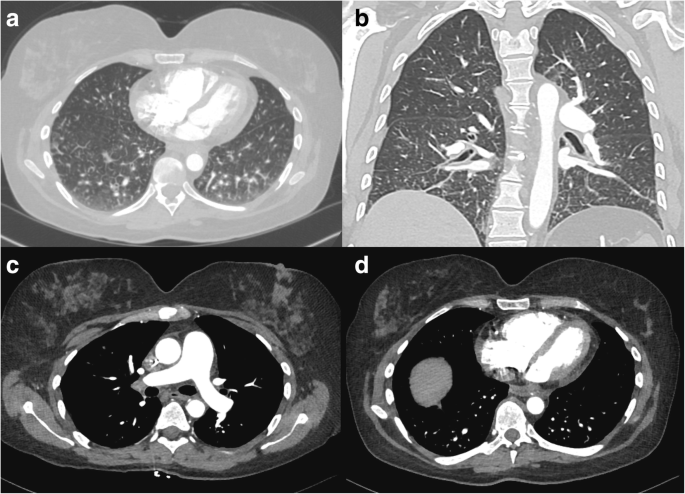

During a routine study clinic visit the patient was found to be in sinus tachycardia. Upon further questioning, the patient noted progressive dyspnea on exertion and fatigue over the previous month and was therefore admitted to the NIH Clinical Center for further evaluation. Vital signs revealed a temperature of 37°C, heart rate of 120 beats per minute, a manual blood pressure of 90/72 mmHg without orthostatic changes and oxygen saturation ranging from 93 to 97% on room air. Physical examination findings were notable for a normal jugular venous pressure, regular heart rate without a prominent P2, clear breath sounds, and warm extremities without edema. Intravenous fluid was administered for possible dehydration due to diarrhea, but symptoms did not improve. A portable chest x-ray revealed hazy bibasilar interstitial markings (Fig. 1). Laboratory studies revealed a hemoglobin of 9.8 g/dL (normal range 11.2-15.7 g/dl), a platelet count of 159 k/μL (normal range 173-369 k/μL), normal coagulation indices (PT 13.8 s; aPTT 35.5 s; thrombin time 15.8 s), a D-dimer of 0.98 μg/mL (normal range 0.00–0.50 μg/mL), a fibrinogen of 517 mg/dL (normal range 177–466 mg/dL), a pro-brain natriuretic peptide of 4541 pg/mL (normal range 0–124 pg/mL) and a troponin-T of 0.022 ng/mL (normal range 0.000–0.009 ng/mL). Echocardiography demonstrated a dilated right ventricle with decreased function (tricuspid annular plane systolic excursion (TAPSE) of 8 mm; normal ≥17 mm) and an elevated right ventricular systolic pressure of 67 mmHg, new findings compared to her baseline echocardiogram completed just 4 months earlier. Cardiac MRI, performed to evaluate for possible treatment related myocarditis, demonstrated severely reduced right ventricular function (ejection fraction of 27%; normal 61±10%) with volume and pressure overload consistent with pulmonary hypertension, but no evidence of myocarditis. A CT angiogram showed no evidence of pulmonary emboli, however there was a prominence of interstitial markings (Fig. 2a, b), the main pulmonary artery was enlarged (Fig. 2c) and the right atrium and ventricle were both severely dilated (Fig. 2d). A ventilation (Fig. 3a) - perfusion (Fig. 3b) scan (VQ) demonstrated mismatched perfusion defects along the pleural margins that were interpreted as a high probability of pulmonary emboli. Doppler ultrasonography revealed no evidence of venous thrombosis in the lower extremities. Despite the equivocal findings, therapeutic anti-coagulation was started for possible pulmonary emboli.

Contrast enhanced CT image with axial (a) and coronal (b) sections demonstrating a prominence of interstitial markings predominantly in posterior and basilar lung fields. In mediastinal windowing accentuating the pulmonary vasculature (c) the pulmonary artery trunk is enlarged and (d) the right ventricle and right atria appear larger in area than their corresponding left sided chambers; findings suggestive of pulmonary hypertension